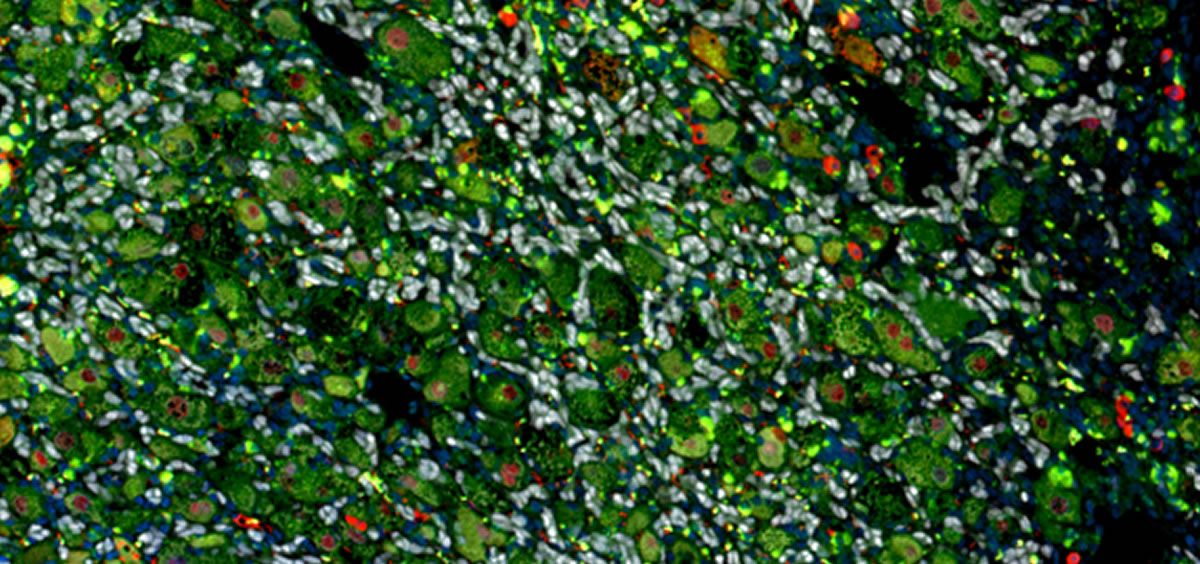

En la cirrosis, el hígado se endurece y se vuelve fibrótico, como tejido cicatrizado, debido a la activación de las células llamadas fibroblastos. El trabajo realizado por el CNIO explica cómo estas células comienzan a funcionar, cuando las células predominantes del hígado, los hepatocitos, no producen una proteína llamada MCRS1, los ácidos biliares se acumulan en el hígado y activan los fibroblastos, que acaban produciendo la fibrosis.

Las investigadoras Amanda Garrido y Eunjeong Kim, primeras firmantes del trabajo, fueron las creadoras del ratón modificado genéticamente de forma que los hepatocitos del animal no expresaran MCRS1, además de observar que de esta manera desarrollaba alteraciones propias de la cirrosis hepática humana.

El descubrimiento principal de este trabajo fueron los mecanismos desencadenantes de esta trasformación y la activación de los fibroblastos.

La falta de MCRS1 en los hepatocitos altera el flujo de los ácidos biliares, y estos ácidos terminan activando en los fibroblastos un receptor molecular, llamado FXR, que pone en marcha el proceso de la cirrosis. “Esta cadena de eventos es central y universal en el desarrollo de la cirrosis hepática, actuar sobre esta vía tendría implicaciones importantes para el tratamiento de la cirrosis”, aclaraba Djouder.